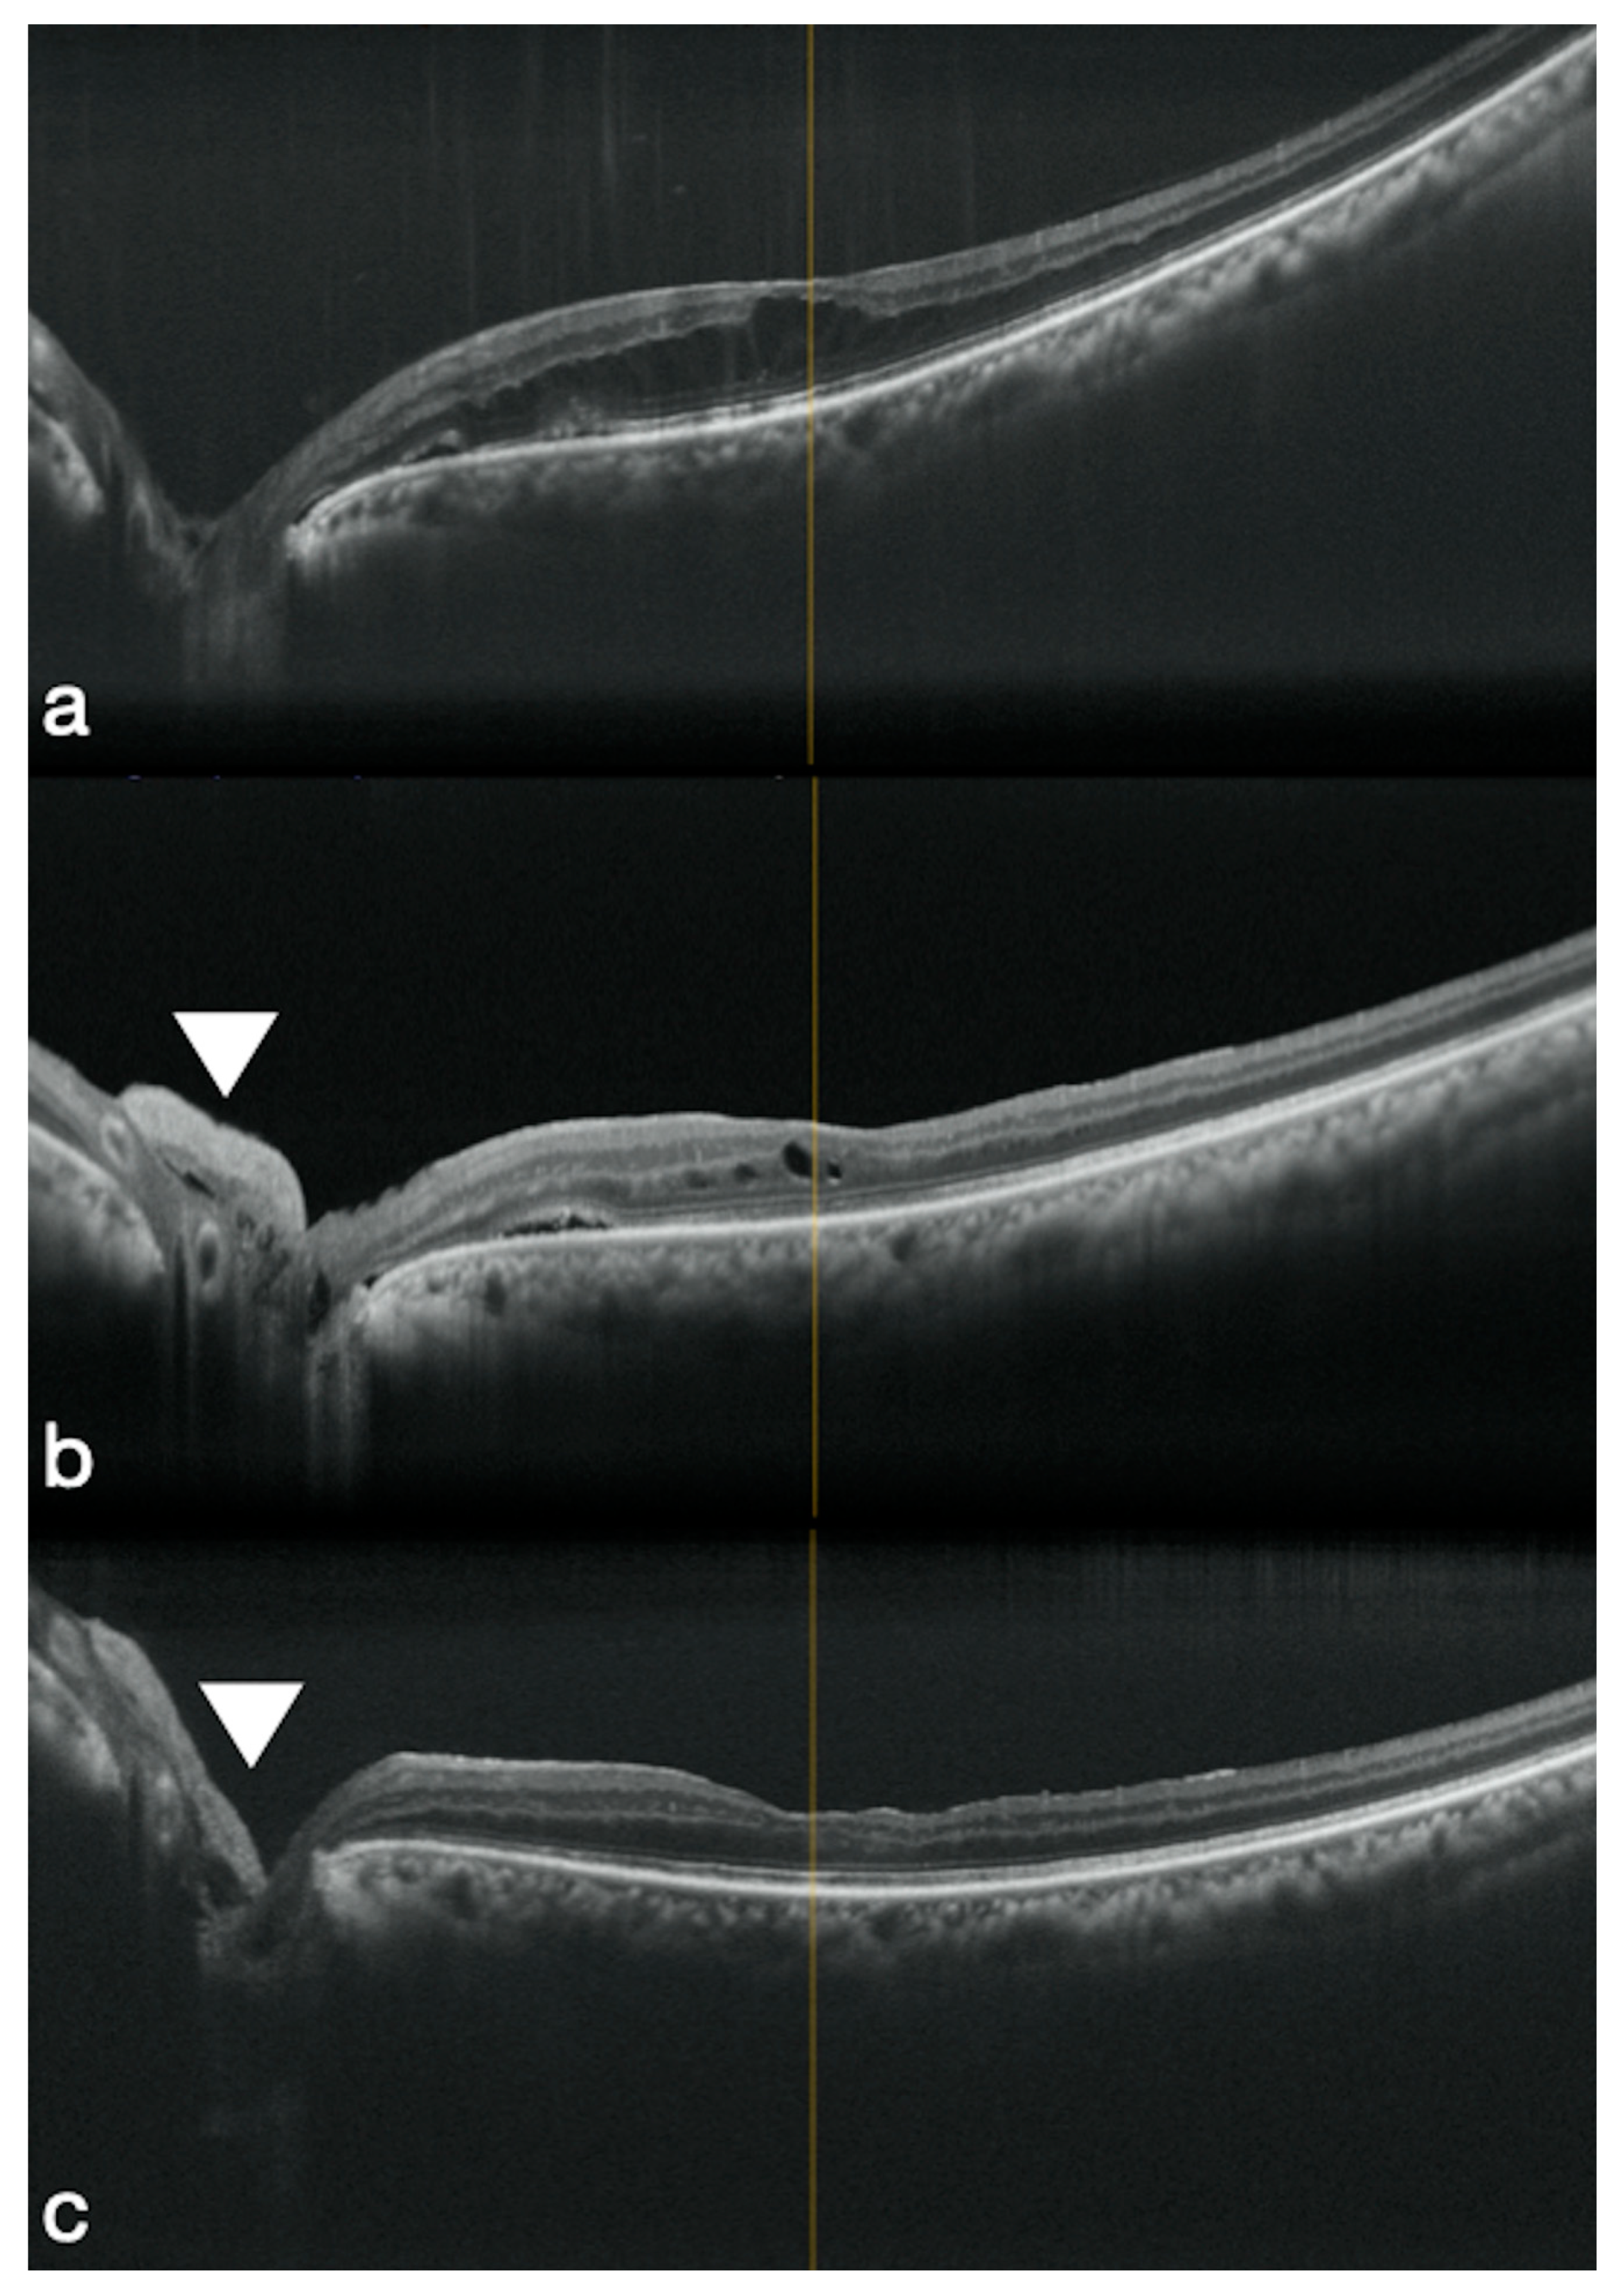

3.2. High Myopic Macular Hole Associated with Retinal Detachment

- Caporossi, T.; De Angelis, L.; Pacini, B.; Tartaro, R.; Finocchio, L.; Barca, F.; Rizzo, S. A human Amniotic Membrane plug to manage high myopic macular hole associated with retinal detachment. Acta Ophthalmol. 2020, 98, e252–e256. [Google Scholar] [CrossRef] [PubMed]

- Caporossi, T.; De Angelis, L.; Pacini, B.; Rizzo, S. Amniotic membrane for retinal detachment due to paravascular retinal breaks over patchy chorioretinal atrophy in pathologic myopia. Eur. J. Ophthalmol. 2020, 30, 392–395. [Google Scholar] [CrossRef] [PubMed]